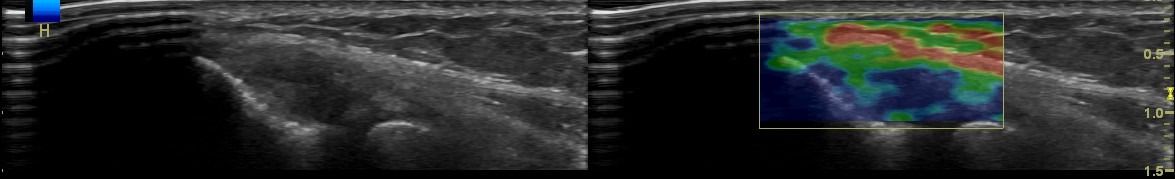

Elbow Ultrasound provides comprehensive imaging of various structures in the region, allowing the identification of pathologic conditions in the joint, bursae, tendons, ligaments, nerves, and soft tissues of the elbow.

- Lateral Epicondylitis (Tennis Elbow)